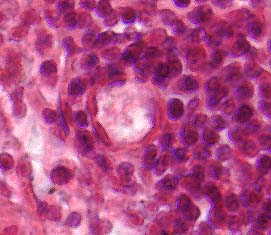

Figure 2. Five histological images of a germinal center where B cells congregate during an infection.